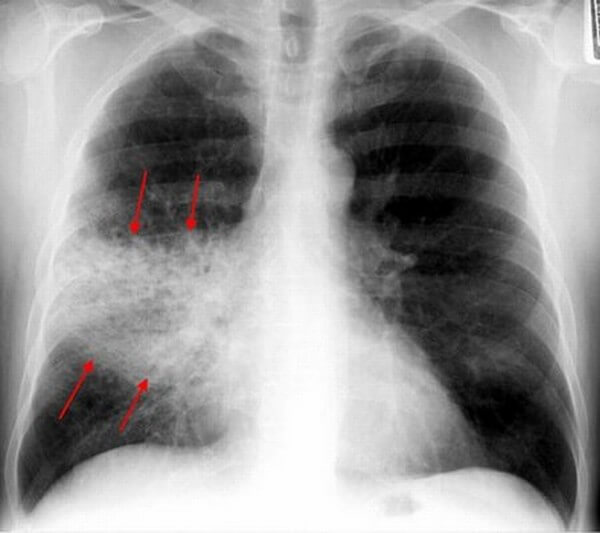

При абсцедирующей пневмонии на снимке отчетливо видно тотальное затемнение области инфильтрации и уплотнение плевры; наблюдаются полости до 2 см, в которых скапливается гнойная жидкость.

Интерстициальная пневмония – поражения очагового или диффузного характера, протекают с инфильтрацией интерстициальной ткани. У детей данная форма пневмонии вызвана вирусами или пневмоцистами.

На снимке наблюдается увеличение сосудистого пучка и увеличение корней легких. Заметным становится интенсивный силуэт «ветки дерева», что является специфическим признаком болезни.

- Интерстициальная форма. На снимке заметно уплотнение корней легких и другие изменения, которые формируют выраженный рисунок, напоминающий ветви дерева.

- Абсцедирующая пневмония. Проявляется обширным затемнением пораженной области, признаками утолщения плевры и наличием полостей разного размера, наполненных жидкостью.